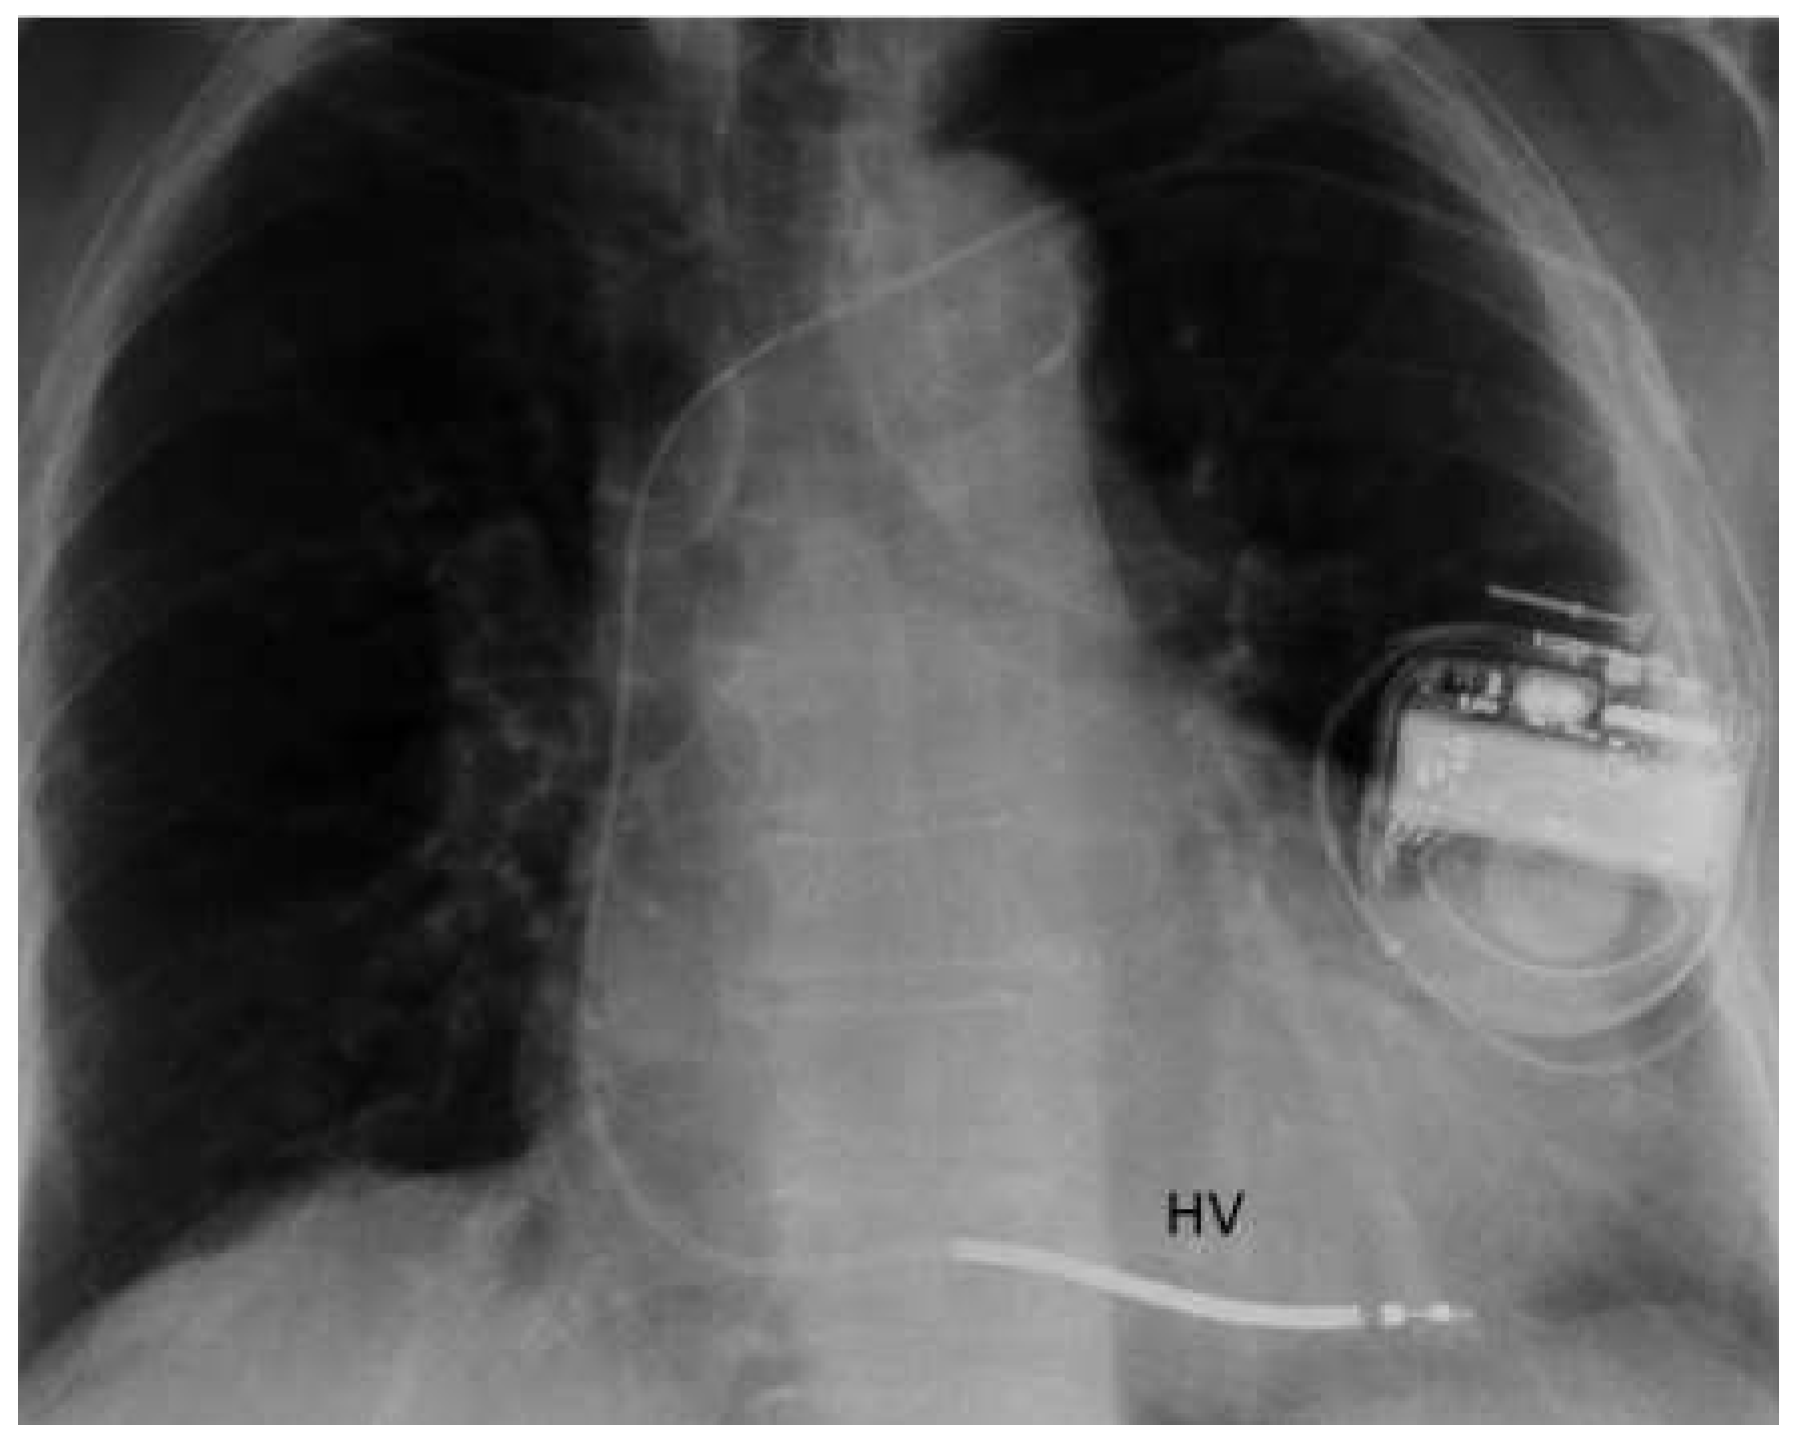

| ICD | implantable cardioverter defibrillator |